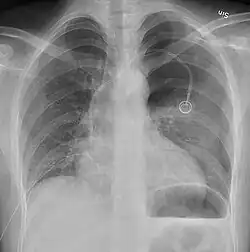

Chest X-ray

A plain chest radiograph, ideally with the X-ray beams being projected from the back (posteroanterior, or "PA"), and during maximal inspiration (holding one's breath), is the most appropriate first investigation.[35] It is not believed that routinely taking images during expiration would confer any benefit.[36] Still, they may be useful in the detection of a pneumothorax when clinical suspicion is high but yet an inspiratory radiograph appears normal.[37] Also, if the PA X-ray does not show a pneumothorax but there is a strong suspicion of one, lateral X-rays (with beams projecting from the side) may be performed, but this is not routine practice.[18][22]

Chest X-ray showing a pneumothorax on the right (left in the image), where the absence of lung markings indicates that there is free air inside the chest -

Chest X-ray showing the features of pneumothorax on the left side of the person (right in image)

It is not unusual for the mediastinum (the structure between the lungs that contains the heart, great blood vessels, and large airways) to be shifted away from the affected lung due to the pressure differences. This is not equivalent to a tension pneumothorax, which is determined mainly by the constellation of symptoms, hypoxia, and shock.[16]

The size of the pneumothorax (i.e. the volume of air in the pleural space) can be determined with a reasonable degree of accuracy by measuring the distance between the chest wall and the lung. This is relevant to treatment, as smaller pneumothoraces may be managed differently. An air rim of 2 cm means that the pneumothorax occupies about 50% of the hemithorax.[18] British professional guidelines have traditionally stated that the measurement should be performed at the level of the hilum (where blood vessels and airways enter the lung) with 2 cm as the cutoff,[18] while American guidelines state that the measurement should be done at the apex (top) of the lung with 3 cm differentiating between a "small" and a "large" pneumothorax.[38] The latter method may overestimate the size of a pneumothorax if it is located mainly at the apex, which is a common occurrence.[18] The various methods correlate poorly but are the best easily available ways of estimating pneumothorax size.[18][22] CT scanning (see below) can provide a more accurate determination of the size of the pneumothorax, but its routine use in this setting is not recommended.[38]

Not all pneumothoraces are uniform; some only form a pocket of air in a particular place in the chest.[18] Small amounts of fluid may be noted on the chest X-ray (hydropneumothorax); this may be blood (hemopneumothorax).[16] In some cases, the only significant abnormality may be the "deep sulcus sign", in which the normally small space between the chest wall and the diaphragm appears enlarged due to the abnormal presence of fluid.[19]